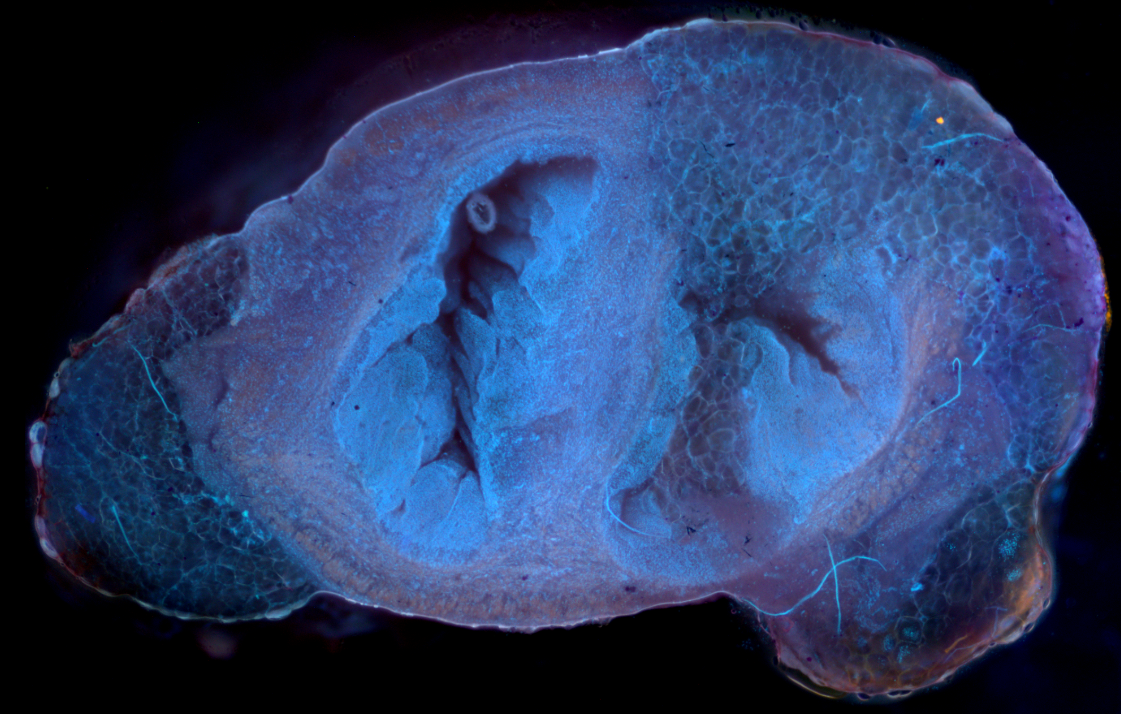

Our latest preprint on our UV microscopy project at NUH has been

posted!